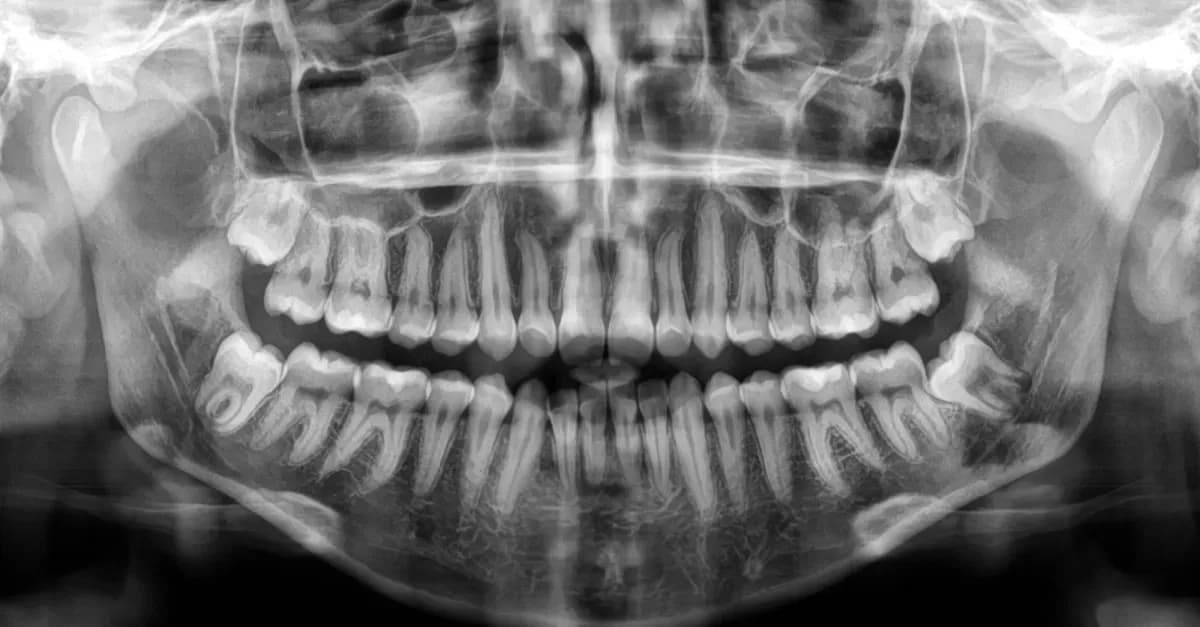

Aby zminimalizować ryzyko powikłań związanych z wzrostem zębów mądrości, warto wprowadzić kilka praktycznych nawyków. Regularne wizyty u dentysty, nawet jeśli nie odczuwasz bólu, mogą pomóc w wczesnym wykryciu problemów związanych z erupcją ósemek. Dentysta może zalecić zdjęcia rentgenowskie, które pozwolą ocenić położenie zębów mądrości oraz zidentyfikować ewentualne zagrożenia, zanim staną się one poważne.